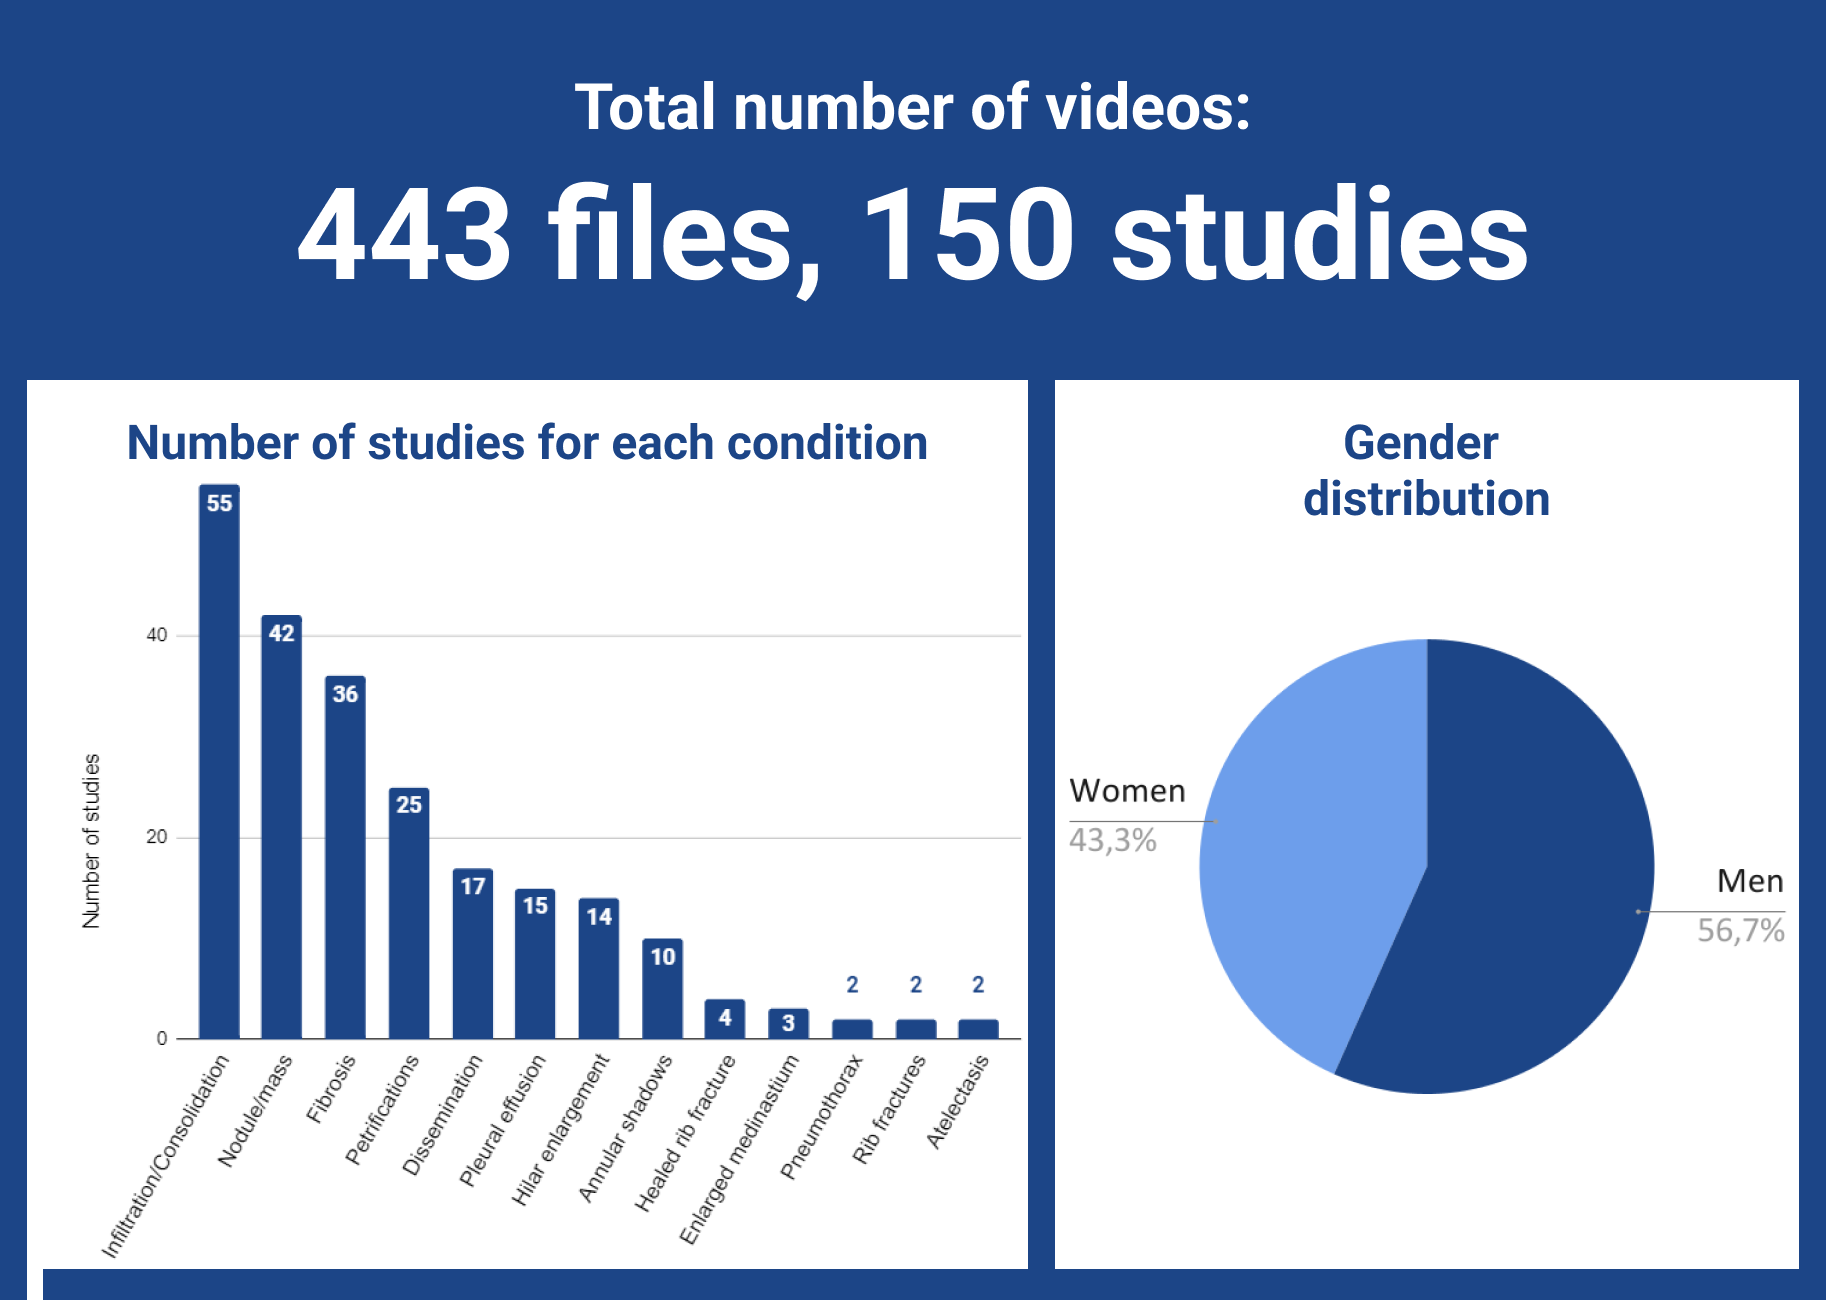

Chest X-rays, DICOM Data and Segmentation

This dataset consists of 150 medical studies with chest X-ray (CXR) images primarily focused on the detection of lung diseases, including COVID-19 cases and pneumonias. The collection includes frontal chest radiographs and chest radiography scans in DICOM format. The dataset is ideal for medical research, disease detection, and classification tasks, particularly for developing computer-aided diagnosis and machine learning models - Get the data

13 classes of labeling:

- Petrifications

- Nodule/mass

- Infiltration/Consolidation

- Fibrosis

- Dissemination

- Pleural effusion

- Hilar enlargement

- Annular shadows

- Healed rib fracture

- Enlarged medinastium

- Rib fractures

- Pneumothorax

- Atelectasis